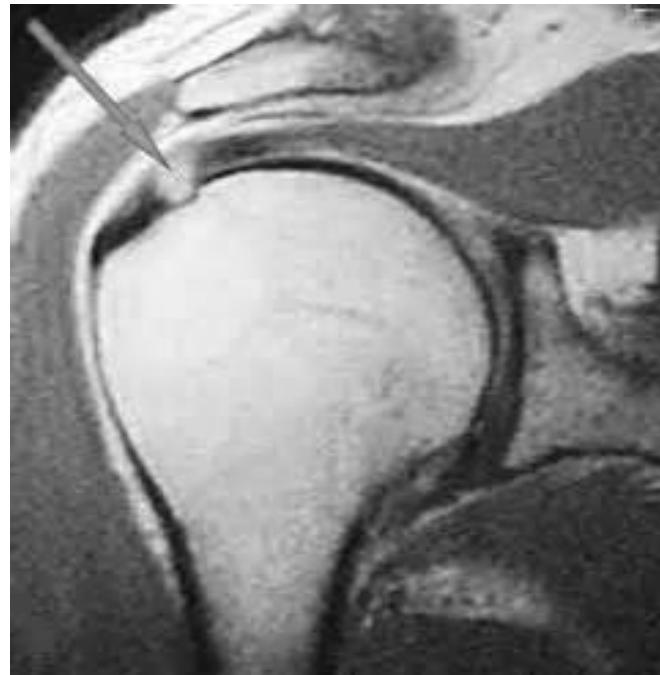

Imaging

Question: What do you see on these images?

Treatment Plan

Indications for Surgery

Since physiotherapy failed and patient has complete tear of rotator cuff muscles:

Surgical Management

- Arthroscopic rotator cuff repair is recommended